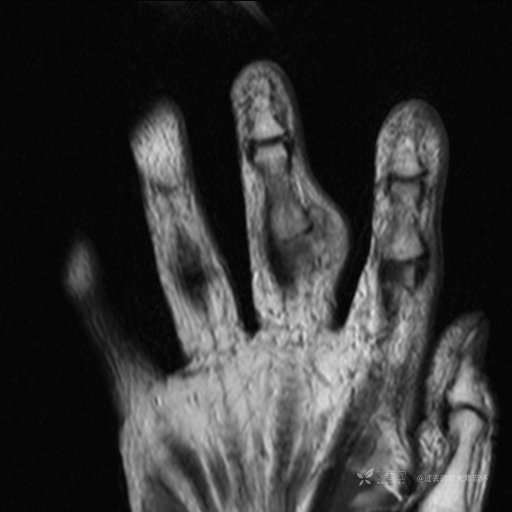

患者性别:女

患者年龄:59岁

主诉: 手指肿胀2年,其间明显肿胀,抗炎后肿胀减轻,近几日肿胀疼痛加重。

T2及T2压脂